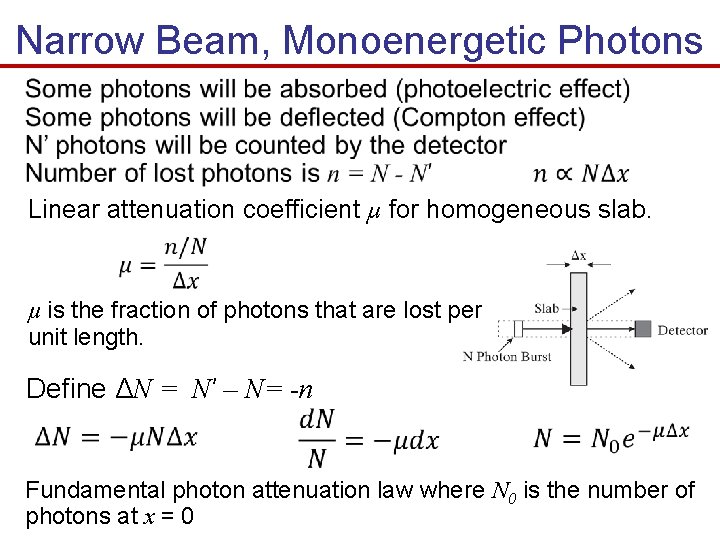

Narrow Beam, Monoenergetic Photons Linear attenuation coefficient µ for homogeneous slab. µ is the fraction of photons that are lost per unit length. Define ΔN = N’ – N= -n Fundamental photon attenuation law where N 0 is the number of photons at x = 0